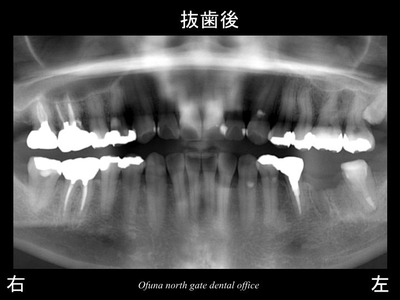

以下は、抜歯後です。

この患者様は、神経がない歯が非常に多いことが分かります。

以下が抜歯後です。

この方も神経のない歯が多いですね。

以下が抜歯後です。